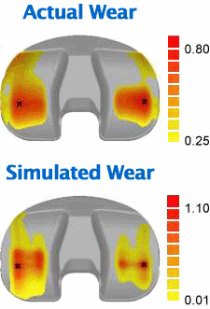

A comparison of the actual knee implant wear with the simulated wear predicted by the computer model. The actual wear was measured from two aligned laser scans, one of the worn tibial insert and the other of an unworn insert of the same size. The team visualized the simulated wear by creating worn surface geometry in Geomagic Wrap (based on outputs from the computer simulation) and then superimposing the data on the unworn geometry in Geomagic Control.

Researchers have been able to compare the simulated wear predicted by an early version of a computational model with the actual wear of an artificial knee recovered from a patient. Their computational model’s prediction came within three-tenths of a millimeter of the actual maximum wear depth and accurately predicted the locations of the worst wear.